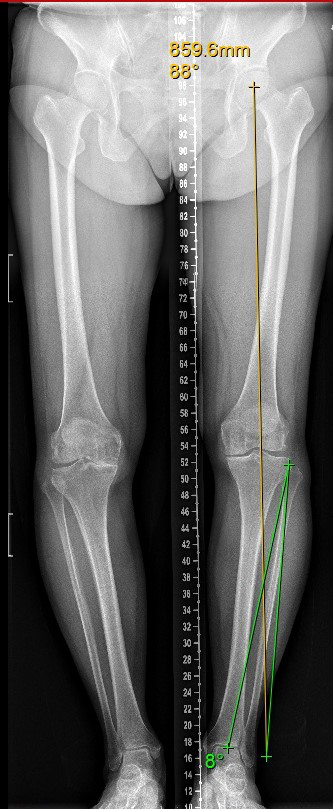

—胫骨高位截骨术(high tibial osteotomy, HTO),是通过胫骨近端微创楔形开槽,改变下肢力线的异常分布,降低内侧间室的压强,将其恢复到软骨能够承受的正常范围,使得受损的膝关节内侧不负重或者少负重,可明显缓解疼痛和改善步态,改善膝关节生物力学环境和有效血液循环,促进内侧间室关节软骨修复,减轻膝关节疼痛,恢复膝关节正常活动。从而避免换关节,或者推迟换关节的时间。特别适合相对年轻活跃、MPTA(胫骨近端内侧角)小于85度或大于90度的内侧骨关节炎患者。临床实践证明,约三分之二的患者并不需要膝关节置换,可以采用保膝手术治疗,有效率甚至超过全膝关节置

选择的优势:由于属于微创手术,创伤小,出血少,对软组织破坏少,所以患者术后锻炼的时间早,并发症少,恢复越快。

术后当天床上活动,术后第2天就开始患肢部分负重,4周开始逐渐增加负重,6-8周后可以完全负重。由于此微创手术不破坏关节内的任何重要结构,包括软骨、交叉韧带、半月板,因此被称为为真正的保膝手术,它可以完整的保留膝关节的功能和本体感觉。手术只相当于一次小腿的不全骨折的愈合,所以术后很少发生关节活动受限的情况,患者不需要很辛苦的进行关节屈伸锻炼,就可以达到关节活动自如。充分体现了“保膝”理念,保留了关节的自然运动功能与舒适性,延长患者膝关节的自然寿命。